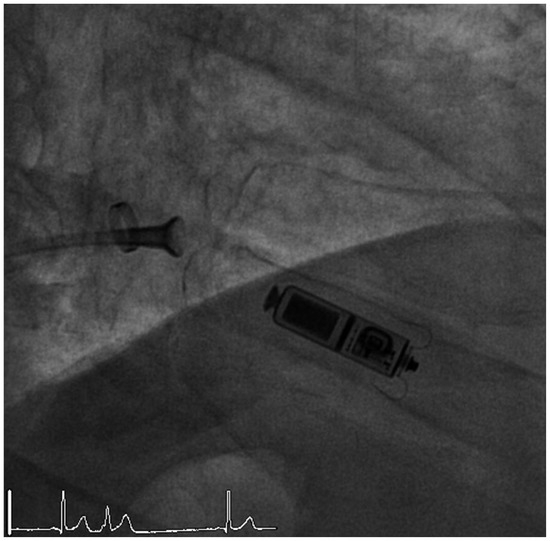

Bradyarrhythmias

by Vanessa Weberndörfer, Ian Russi and Richard Kobza

Cardiovasc. Med. 2018, 21(9), 218; https://doi.org/10.4414/cvm.2018.00580 - 19 Sep 2018

Pacemaker implantation is indicated when symptoms can clearly be attributed to bradyarrhythmias or in asymptomatic patients with type 2 second degree atrioventricular (AV) block or complete heart block. First-degree AV block or Mobitz 1 second-degree AV block usually do not need any intervention [...] Read more.

Pacemaker implantation is indicated when symptoms can clearly be attributed to bradyarrhythmias or in asymptomatic patients with type 2 second degree atrioventricular (AV) block or complete heart block. First-degree AV block or Mobitz 1 second-degree AV block usually do not need any intervention unless there are signs of an infranodal AV block. Biventricular pacemakers and implantable cardioverter defibrillators should be considered in patients with a pacing indication and reduced left ventricular ejection fraction. Prior to pacemaker implantation reversible causes of bradyarrhythmias should be excluded. Atropine should only be administered in intranodal AV block, as there is an elevated risk of causing asystole in infranodal block. Full article

Show Figures

Figure 1